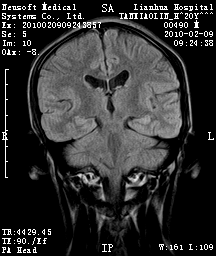

20岁男性患者,平时偶有头痛而无其他不适,现因持续头痛服药后无缓解而来院就诊。

松果体囊肿?

松果体区占位继发轻度脑积水?该患者有ct资料,我已发上。

考虑松果体囊肿。